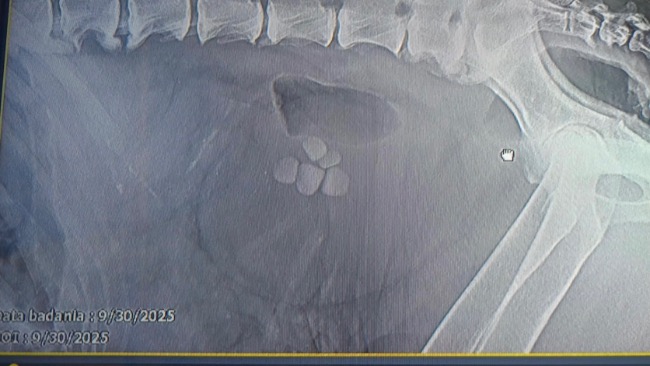

Koszty operacji i rekonwalescencji przerastają możliwości pana Łukasza i jego rodziny. Zwrócili się do nas o pomoc w tej nierównej walce. U Bory stwierdzono duże kamienie w pęcherzu moczowym oraz podwyższone parametry mocznika i kreatyniny. Lekarze zalecili pilną operację ratującą życie, a stan Bory jest bardzo poważny i zaawansowany.